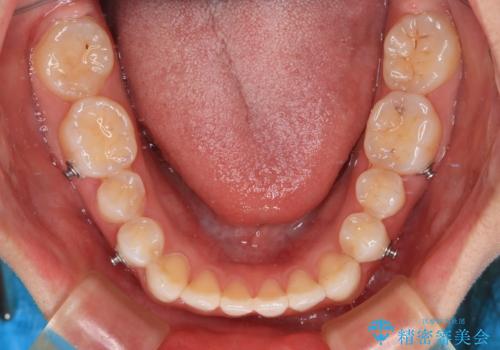

上下前歯同士の距離が離れているため、上顎左右第一小臼歯2本を抜歯することで前突を改善することとしました。

しかしながら、左右ともに側切歯が矮小歯であるため、矯正治療で矮小歯前後にスペースを作り、矯正治療後にオールセラミッククラウンにて補綴治療を行うこととしました。

治療途中で地元へ転居され、飛行機での通院となったため、治療期間が長くなりましたが、自然で整った口元に仕上げることができました。